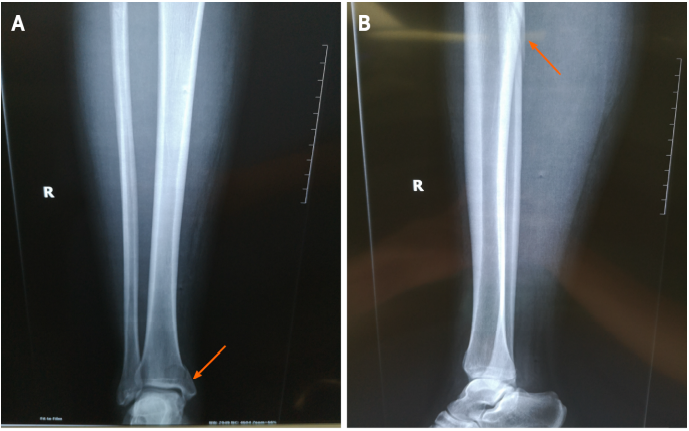

1位31岁女性患者在5天前步行时不小心扭伤了右脚踝。小腿的全长X线片显示腓骨近端骨折,下胫腓关节分离,内踝骨折累及后踝。磁共振成像显示胫腓前下韧带和距腓前韧带断裂。我们诊断出一种罕见的Maisonneuve骨折类型,合并腓骨近端骨折、下胫腓关节分离、内踝骨折以及胫腓前下韧带和距腓前韧带断裂。患者接受切开复位内固定术,术后6个月随访,临床效果良好。(此患者同时具有旋前外旋踝关节骨折和旋后内收踝关节骨折的特点。本例腓骨骨折呈长斜骨折,骨折线靠近腓骨。还有下胫腓分离。这些特征与典型的Maisonneuve骨折相似,后者是一种旋前外旋踝关节骨折。而内踝典型的旋前外旋踝关节骨折通常表现为三角韧带的斜位断裂,而不表现为距腓前韧带或跟腓断裂(11)。本例踝内侧骨折为垂直骨折,距腓骨前韧带断裂,与旋后内收踝关节骨折一致。

图1;A:术前踝关节和小腿正位X线片(箭头);B:术前踝关节和小腿侧位X线片(箭头)。小腿全长X线片显示腓骨近端骨折(箭头)和内踝骨折(箭头)